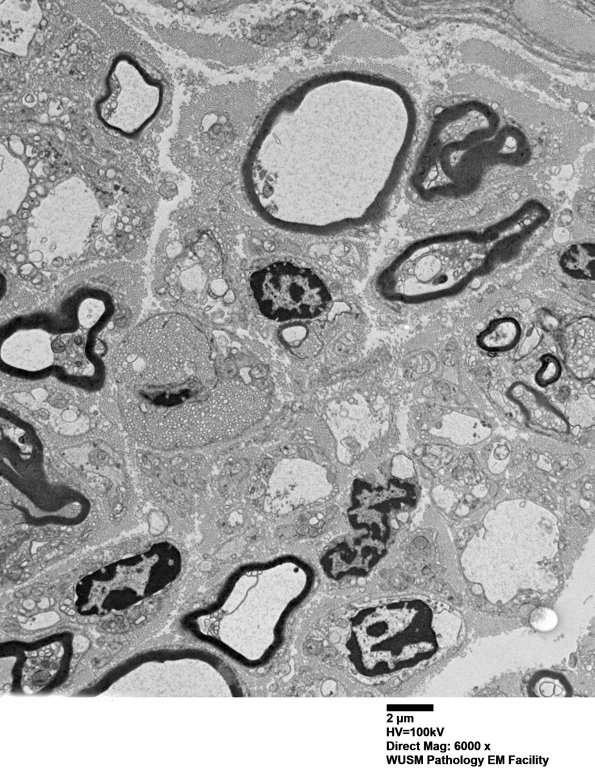

7B2,3 Notice that a number of the large pale non-myelinated axons have the same pallid axoplasm as do the myelinated axons.